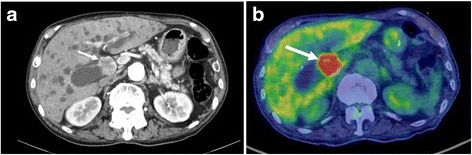

An abdominal computed tomography (CT) scan revealed an enhanced mass that was approximately 2.5 cm in size located in the mid common bile duct (CBD) and an enlarged regional node in the hepatoduodenal ligament (Fig. 1a). 18F-fluorodeoxyglucose positron emission tomography (FDG-PET) revealed high accumulation of FDG with a maximum standardized uptake value (SUVmax) of 20.7 by the CBD tumor (Fig. 1b).